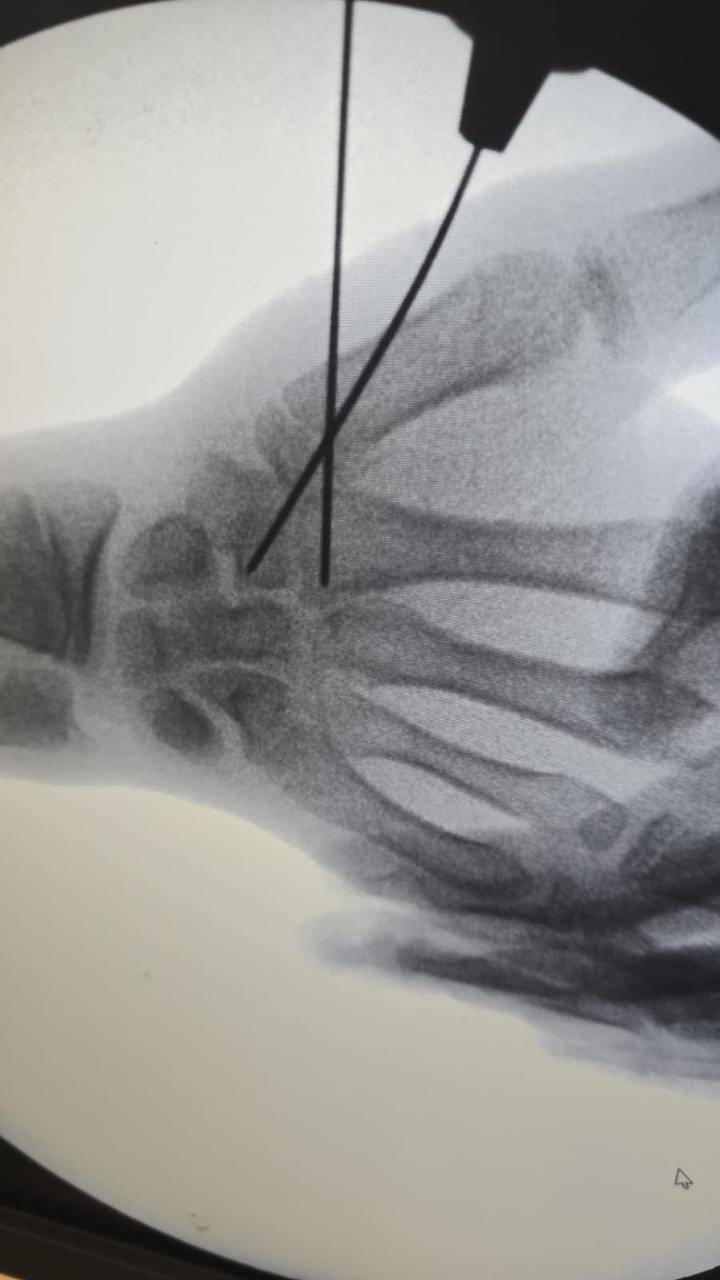

- إجراء عمليات جراحية معقدة و دقيقة في مجال العظام و المفاصل و الكسور و الإصابات ، رغم الضغط الكبير على المستشفى و أعداد المراجعين الكبيرة.

- تطبيق تقنيات جراحية حديثة و متقدمة، و ذلك في ظل التحديات التي يواجهها الفريق بسبب أعداد المرضى و المراجعين الكبيرة.